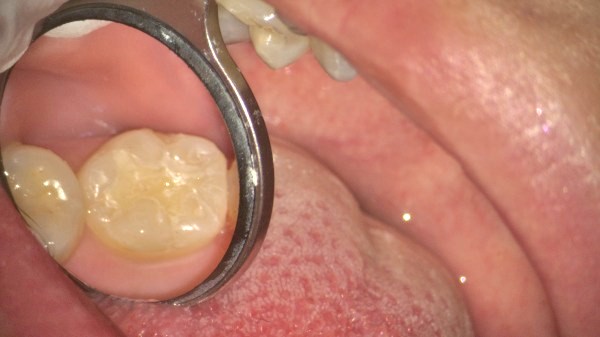

プラスチックは茶色く変色し、縁は黒ずんでいます。歯と歯の間は、凹んでいるためフロスも通しづらい状態でした。さらに詳しく調べるために口腔内エックス線も撮影し、詰め物の大きさを確認することにしました。

1日目 プラスチックを除去し、虫歯の部位を染める「うしょく検知液」で染色ながら虫歯を取り除いていきました。型取りを行い仮の材料を充填しました。

2日目 出来上がってきたセラミックを接着性セメントで装着しました。